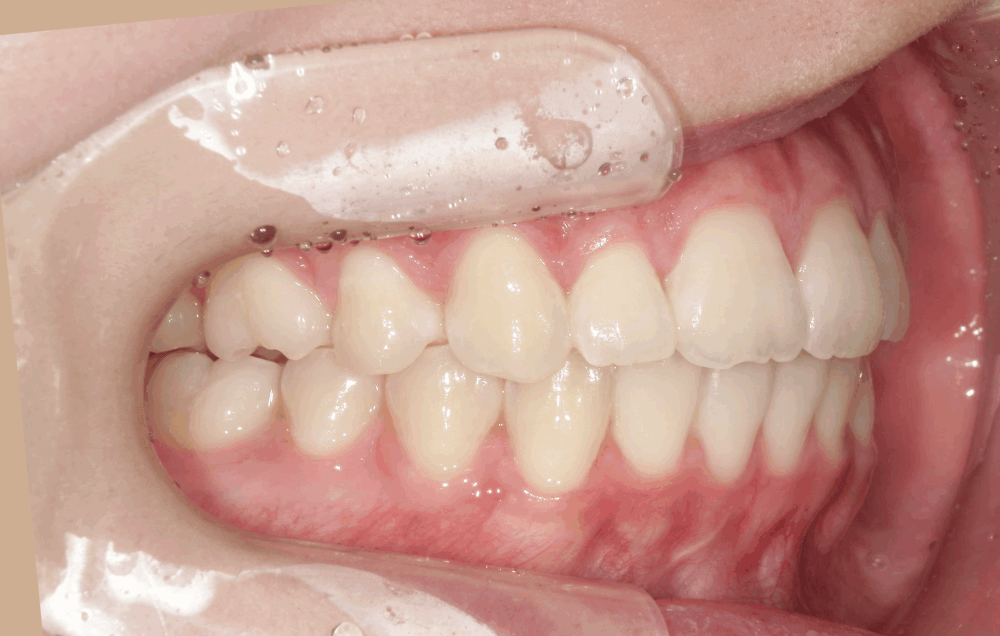

治療後の写真では、歯並びのガタつきが整い、前歯の角度も自然に改善されています。

Eラインに対してもバランスが取れ、力を入れなくても唇を閉じられる、リラックスした口元になりました。

「口元の力みがなくなって、表情が自然になった」と患者様にも喜んでいただけました。今回のような出っ歯や叢生のケースでは、“どれだけ引っ込めるか”だけではなく、“口元の自然さをどう保つか”がとても大切です。

治療前後の比較

治療前

治療後(15か月)